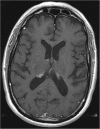

Case presentation: We describe the first reported case of presumed neurosarcoidosis as an immune-related adverse effect that developed nearly a year after discontinuation of treatment with combination ipilimumab and nivolumab for recurrent metastatic melanoma. The patient was noted to develop clinical signs consistent with systemic sarcoidosis shortly after the initiation of treatment and underwent a biopsy of hilar lymphadenopathy that confirmed sarcoidosis and after which immunotherapy was discontinued. His melanoma remained stable on surveillance imaging for the next year after which time he developed neurological symptoms and was found to have MRI brain abnormalities without evidence of intracranial metastatic disease, consistent with probable neurosarcoidosis given biopsy-proven systemic sarcoidosis and lack of evidence of CNS infection or malignancy. He underwent treatment with high dose steroids, followed by infliximab, and then methotrexate with both clinical and radiographic improvement within 4 months of starting treatment.

Conclusions: Immune-related adverse effects often occur within 3-6 months of receiving immune checkpoint inhibitor therapy, with some reports of late toxicity. This report highlights a case of probable neurosarcoidosis nearly a year after discontinuation of immune checkpoint therapy. The potential for durable responses after discontinuation of therapy also likely underscores a potential for late toxicity. In patients presenting with new or unexplained symptoms after checkpoint inhibitor therapy, the index of suspicion for an immune-related adverse effect should remain high, irrespective of timing.